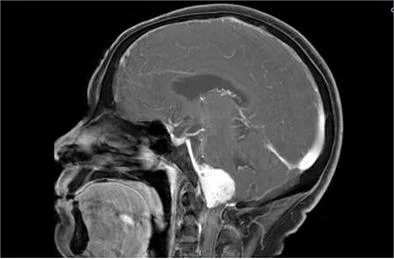

影像学检查包括CT和MRI是常用的诊断工具。CT检查可以较好地显示肿瘤的骨性结构,而MRI具有更高的软组织分辨率,可以更清晰地显示肿瘤的边界和内部结构。